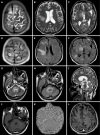

Background: Acute hemorrhagic leukoencephalitis (AHLE), also known as Weston-Hurst syndrome, is a very rare and fulminant form of demyelinating disorder. It is considered a hyperacute and severe variant of acute disseminated encephalomyelitis. Clinically, patients present with fever, headache, seizures, and altered sensorium, which can rapidly progress to coma or death. Magnetic resonance imaging (MRI) is the investigation of choice and plays a pivotal role in diagnosing AHLE. The purpose of this article is to make readers familiar with the typical MRI features of AHLE and to discuss differentials.

Case summary: This case series reports the clinical presentation and typical neuroimaging findings in four patients diagnosed with AHLE. All patients presented with acute neurological symptoms, such as severe headaches, seizures, and altered consciousness, often following a history of fever suggesting an infectious etiology. Additionally, laboratory investigations demonstrated elevated levels of serum inflammatory markers and neutrophilic pleocytosis on cerebrospinal fluid analysis, supporting a post-infectious etiology. MRI findings consistently revealed characteristic white matter lesions with hemorrhagic foci and vasogenic edema, indicative of widespread demyelination characteristic of AHLE. The outcomes varied, with two patients surviving but experiencing neurological sequelae, while two others unfortunately succumbed to the disease. The clinical data, laboratory results, and imaging findings from this case series were systematically compared with those from previously published studies. The key similarities and differences in clinical presentation, imaging characteristics, and outcomes are presented in a tabulated format.